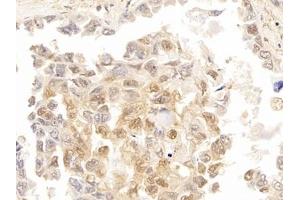

• Immunohistochemistry (IHC)

• Immunohistochemistry (Paraffin-embedded Sections) (IHC (p))

• Immunohistochemistry (Formalin-fixed Sections) (IHC (f))

• Immunohistochemistry (Fixed) (IHC (fx))